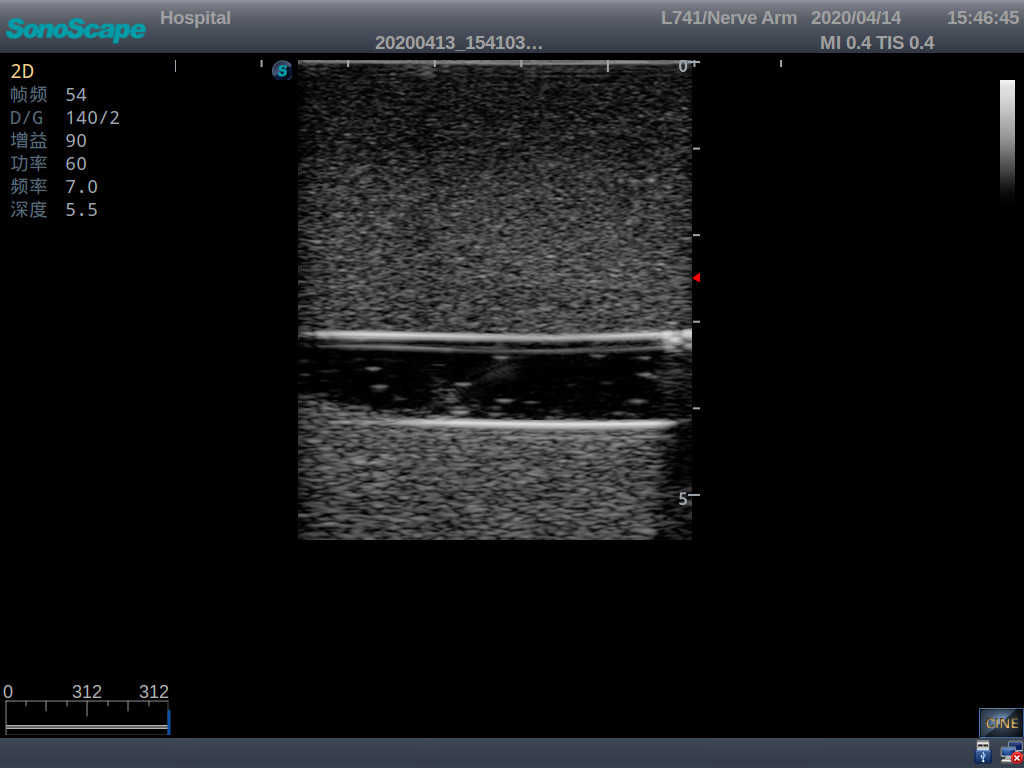

PICC Ultrasound Training Model

Model TYE1510.1

Outline

It is a model covering up from lobulus auriculae plane to the umbilical plane, and it has anatomical structures like clavicle, rib, sternocleidomastoid, jugular vein and basilic vein.

Skills Gained

· PICC training

· Trocar puncture

· Skin dilation with the expander

· Insert the catheter into the central vein along the guide wire

Features

1)   Made of high molecular polymer ultrasound material, close to the real skin

2)   It can be used by real ultrasound machines

3)   Clear and real images of the tissues and organs (basilic vein and superior vena cava)

4)   When conducting vascular puncture, the piercing can be truly felt, and venous blood outflow can be seen

5)   Observe the guide wire marches

6)   Detect whether the catheter is properly placed

7)   Modules of the puncture position are replaceable